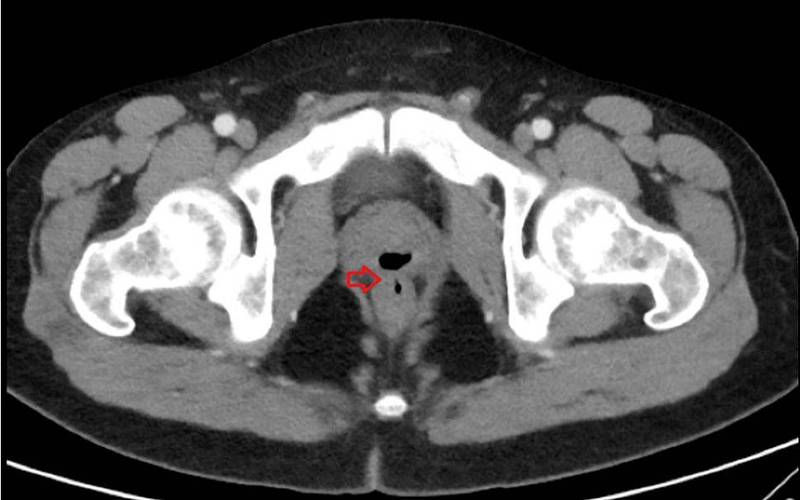

透過CT報告也可見,男子的直腸與尿道之間有一稱為「瘻管」(Fistula)的異常管道,因內部充滿空氣,導致尿道產生了大量氣體,隨著尿液一起排出,就如同放屁一樣,這種症狀則被稱為「氣尿症」(Pneumaturia),日前男子的前列腺和直腸經手術後,留下了一條「隧道」供氣體正常排放,並透過服藥治療發炎、腫脹的睪丸。